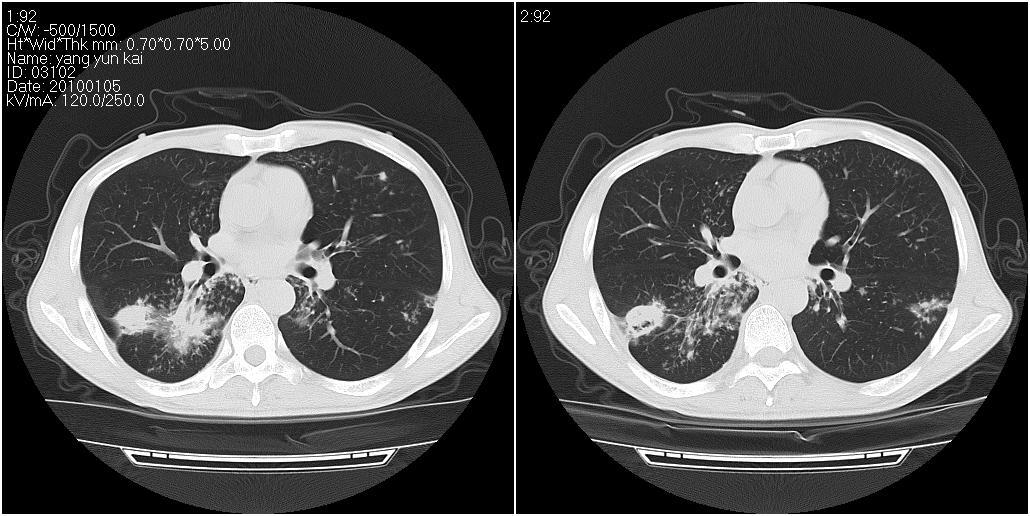

标题: CT23980:男性,47岁。近来咳痰、咳血,血沉增快(40左右),

男性,47岁。近来咳痰、咳血,血沉增快(40左右),痰中未检出结核杆菌。

两肺继发性肺结核并多发性结核球形成,部分病灶内空洞形成。